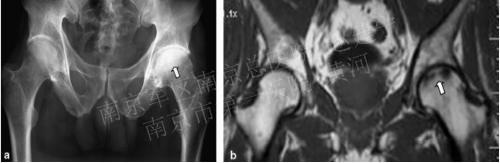

病损周围环绕硬化带(白箭头)软骨下骨折(黑箭头)以及关节间隙狭窄(细长白箭头)

股骨头坏死进展性变化:病损周围硬化带

(白箭头),关节面塌陷,关节间隙严重狭窄,

髋臼软骨下囊肿形成(细箭头)